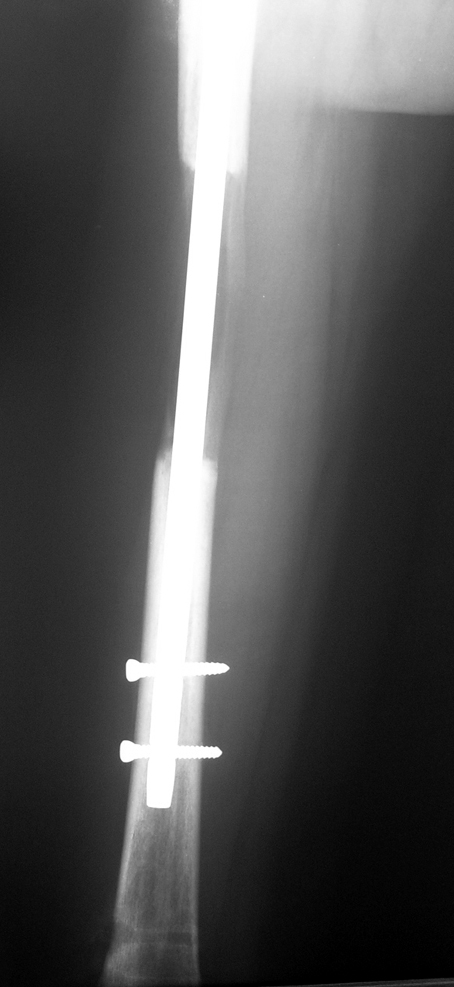

İntramedüller çivinin yerleştirilmesi ve osteotomi: Hasta traksiyon masasına supin pozisyonda yatırılır ve sağlam bacak altta olacak şekilde bacaklar makas pozisyonuna alınır. Standart yolla piriformis çukurundan medulla içine girilir ve kılavuz tel üzerinden kullanılacak çividen 1.5 mm daha kalın oyucu ile medulla oyulur. Proksimal femur, çivinin proksimali daha kalın olduğu için daha kalın oyulur. Radyografide osteotomi hattı planlaması yapılır. Planlama yapılırken uzatma sonunda distalde en az 8 cm. çivi kalması stabilizasyon için gereklidir. Kortikotomi perkütan olarak kortikotom ile tamamlanır. Daha sonra kılavuz tel çivinin boyunu ölçmek için distale ilerletilir. Uygun boyda intramedüller çivi çakılır. Son olarak çivi proksimalden kilitlenir ve bir adet dren konarak ameliyatın birinci kısmı tamamlanır.

Biz son zamanlarda, seçilmiş vakalarda, uzatma sonrası uzunluğu ve “alignment’ı” korumak amacı ile unilateral dinamik aksiyel fiksatör ve kilitli intramedüller çivi kombinasyonunu tercih etmekteyiz. Bu yöntemin ön şartları medullanın en dar çapının 7 mm.’den geniş olması ve uzatma sonrası distalde en az 8 cm. uzunluğunda çivi kalabilmesidir. İntramedüller çivi hem uzatma esnasında femurun üzerine gelen makaslama ve bükülme kuvvetlerini nötralize etmekte hem eksternal fiksasyon süresini kısaltmakta, hem de yeni oluşan kemiği kırıklara karşı korumaktadır. Serimizde bir vakada subtrokanterik femoral osteotomi yapılmıştır. İntramedüller çiviye rağmen varus angulasyonu oluşması yönünde bir dezavantaj tespit etmedik.

İlizarov, distraksiyon osteogenezisi için endosteal kan dolaşımının önemini vurgulamıştır. Biz tüm vakalarımızda femuru oyarak intramedüller çiviyi çaktık; buna rağmen hiçbir vakada kallus oluşma süresi tahminimizden daha uzun olmadı. Bu yüzden medüller dolaşımın bozulmasına bağlı yeni kemik oluşma hızında bir yavaşlama olmadığını düşünüyoruz. Oyma sonrası meydana gelen revaskülarizasyon, intramedüller çivili fiksasyon stabilitesi ve erken fonksiyonel yüklenme bu gerçeğin temelini oluşturmaktadır. Eksternal ve internal fiksasyon yöntemlerinin kombine kullanımının potansiyel dezavantajları kan kaybının artması, intramedüller infeksiyon, yağ embolisi olasılığı ve aşırı metal yüküdür. Bunların içinde en çok korkulan problem bir çivi dibi infeksiyonun tetikleyeceği derin intramedüller infeksiyondur (panosteomyelit). Bizim serimizde bu yönde hiçbir komplikasyon gelişmemiştir. Bu olası komplikasyonun önlenmesi amacı ile uzatma sonundaki kilitleme medialden yapılmalıdır; ayrıca intramedüller çivi ve eksternal fiksasyon pinlerinin teması önlenmelidir.